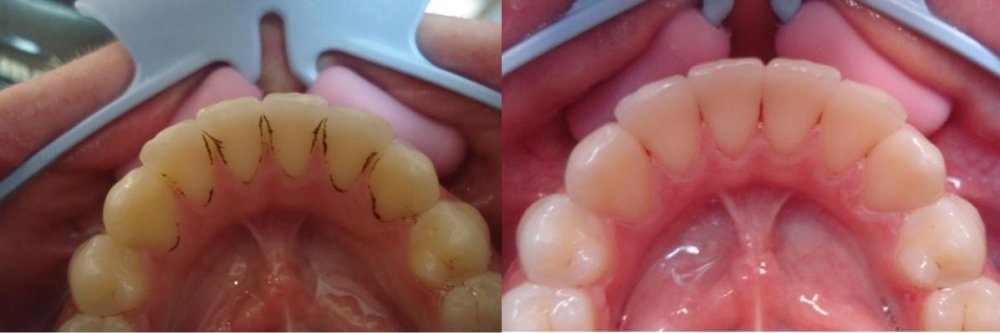

Профилактика кариеса: фото до и после